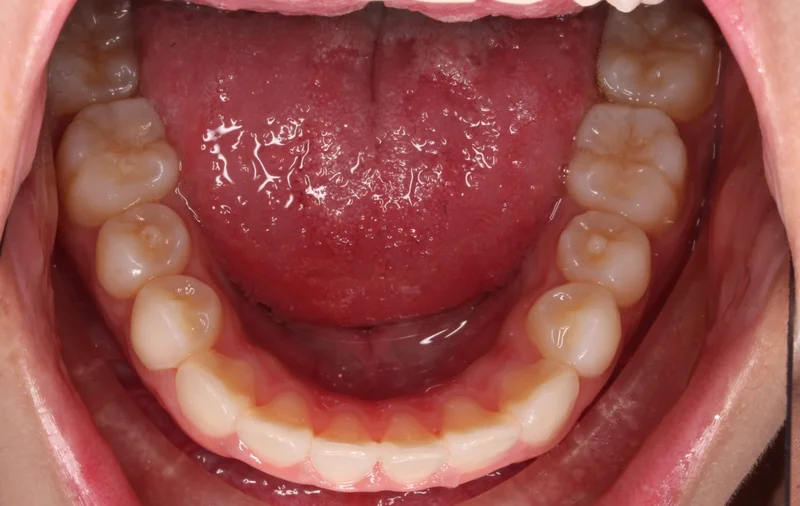

Lower

Lower - Before Treatment

Before